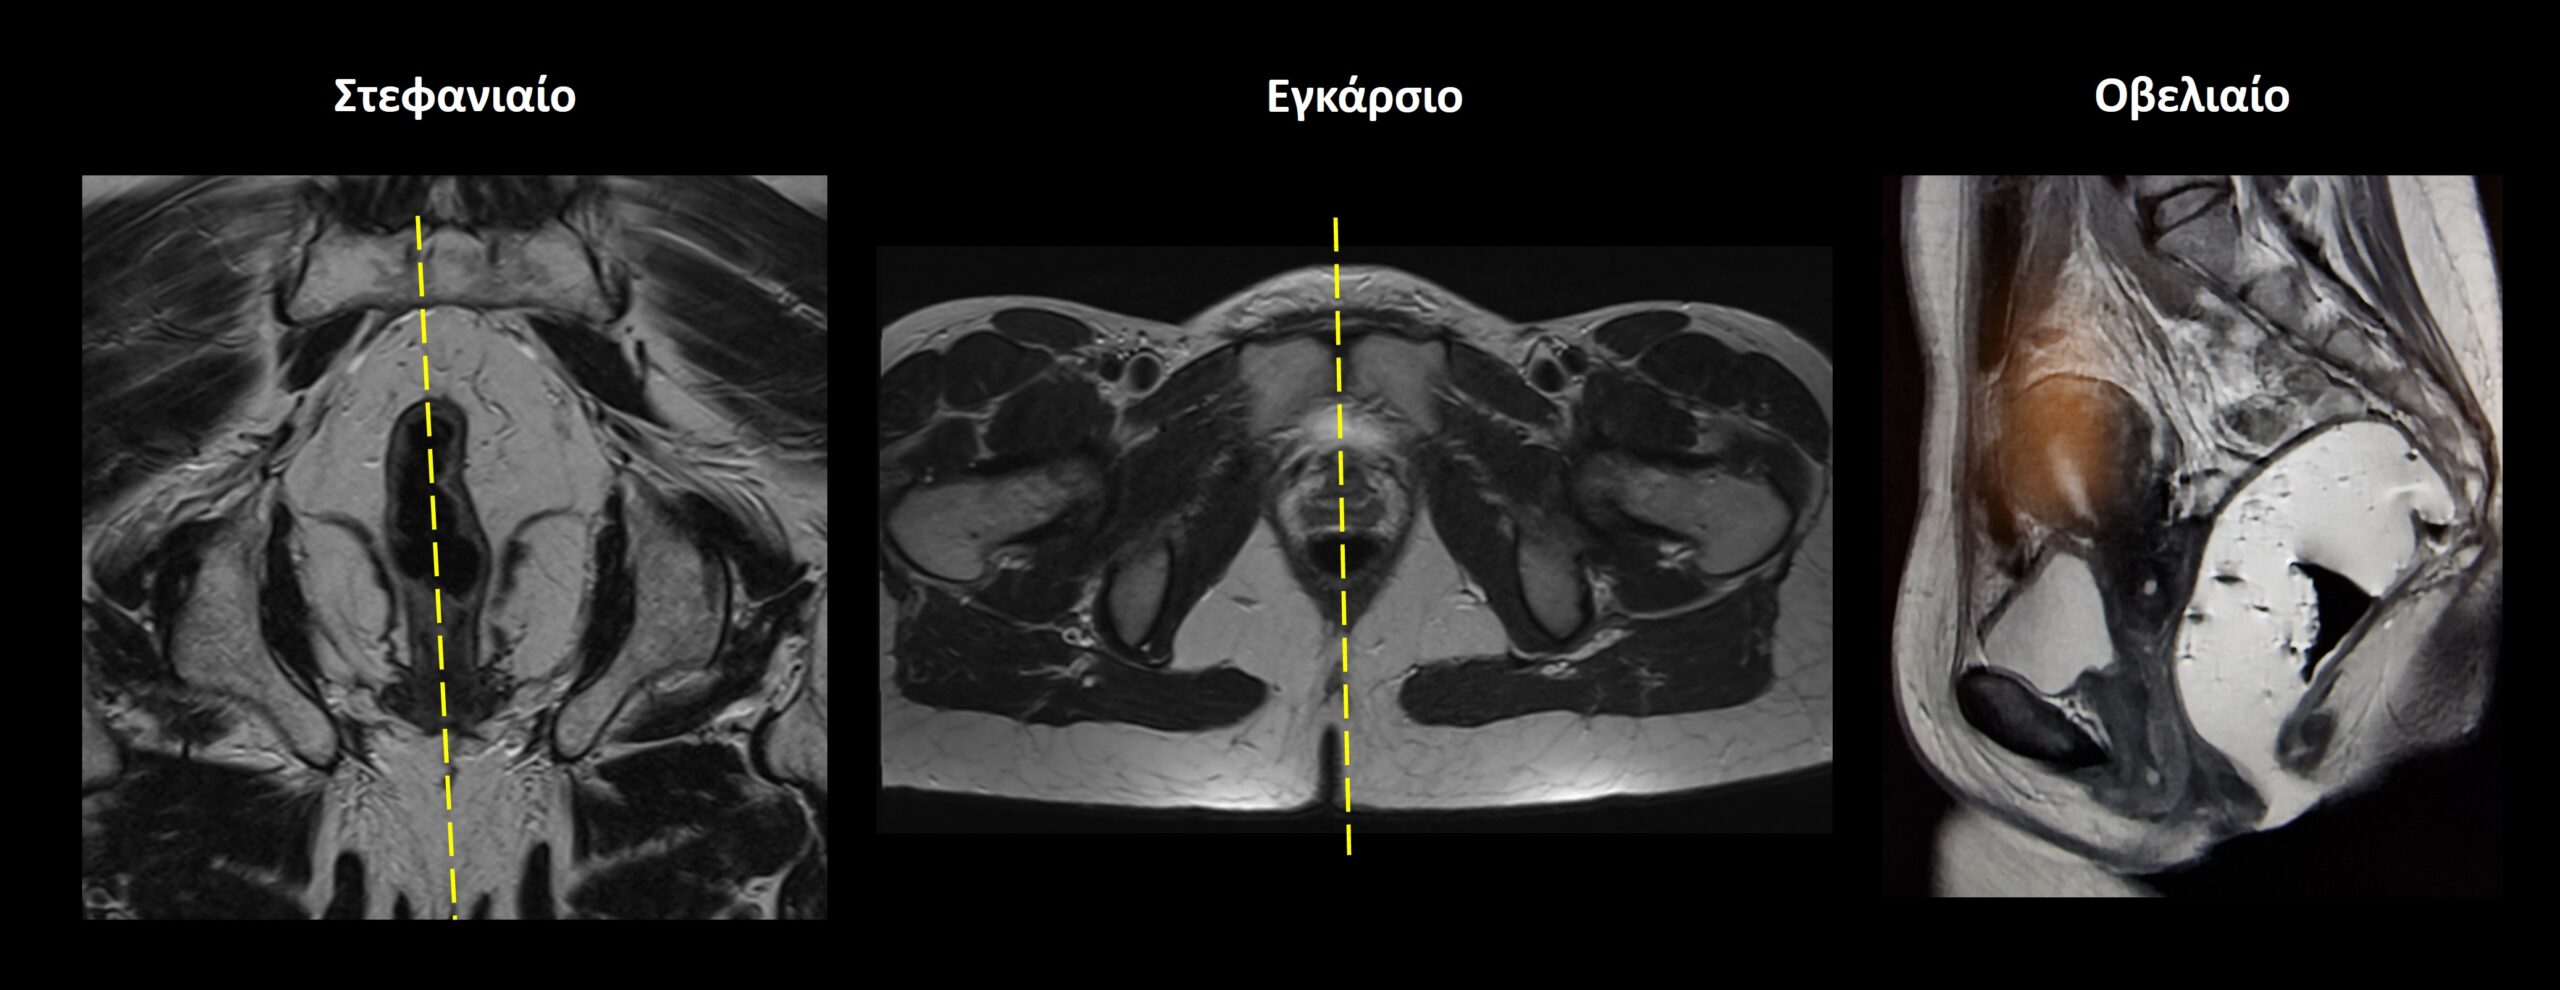

Σχεδιασμός τομών Δυναμική Ακολουθία

• Οβελιαίο επίπεδο (Sagittal): χρήση μίας μοναδικής τομής πάχους 10-15 mm, η οποία σχεδιάζεται παράλληλα με το ορθό και τον πρωκτικό σωλήνα στο στεφανιαίο επίπεδο. Κατάλληλη κλίση πρέπει να δοθεί και στο εγκάρσιο επίπεδο, παράλληλα με τη νοητή γραμμή που ενώνει την ηβική σύμφυση με τον πρωκτικό σωλήνα. Επίσης, η τομή πρέπει να τοποθετηθεί στη μέση του ορθού και του πρωκτού.